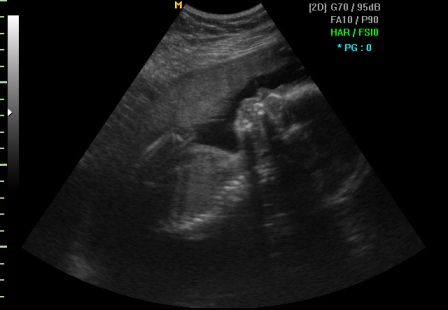

На подолната слика е прикажано мерење на NT и присуството на назалната коска, значајни маркери за откривање на вродените малформации кај плодот.

Вториот скен се закажува за 12. гестациска недела, како прв скрининг преглед во бременоста за Down – ов синдром. На овој преглед се мери нухалната транслуценца (NT), што претставува еден специфичен кожен набор на вратот на бебето, се визуелизира и носната коска на бебето и др. Доколку постои сомневање за Down –ов синдром или некое друго хромозомско пореметување може да се предложи испитување на плодовата вода (амниоцентеза). Вториот скрининг преглед се закажува од 18. до 22. недела од бременоста, и овој преглед претежно служи за откривање на вродени малформации. Сега плодот е веќе доволно развиен и може да се испита феталната анатомија, се врши преглед на плодот по органи и органски системи. Во овој период се одредува локализацијата на плаценатата, а може веќе со сигурност да се потврди и близначката бременост доколку ја има.